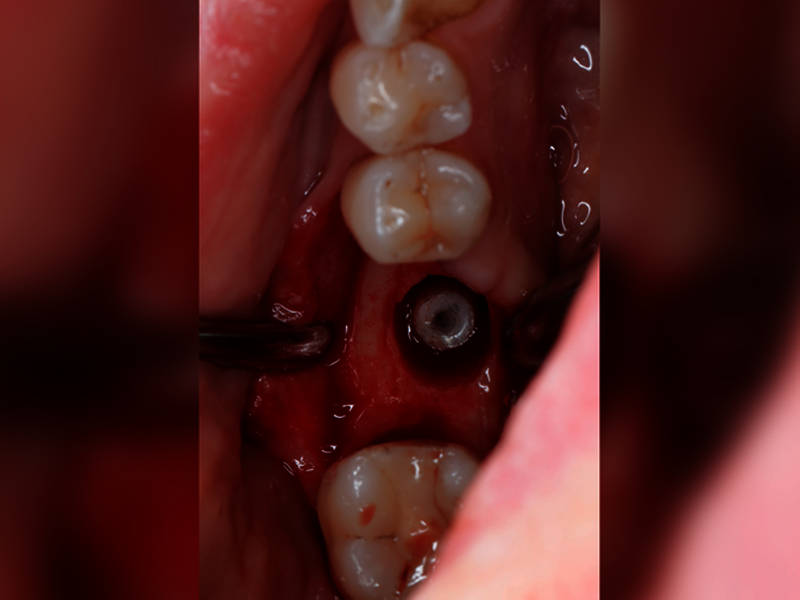

Wenn wir über technische Komplikationen in der Implantologie nachdenken, dann fallen uns sicher zuerst Dinge wie Keramikabplatzungen der Suprakonstruktion, Schraubenlockerungen, Gerüstfrakturen oder Retentionsverluste ein. Schraubenbrüche und Abutmentbrüche gehören Gott sei Dank nicht zu unserem Alltag, genauso wenig wie die schlimmste technische Komplikation: der Bruch des osseointegrierten Implantats (Abbildungen 1 und 2). Sicher kennen die meisten Kolleginnen und Kollegen aus ihren Praxen frakturierte Implantate als eher seltene Ereignisse – die jedoch meist einen sehr großen Behandlungsaufwand nach sich ziehen. Aber wie viele Implantate brechen wirklich beziehungsweise wie hoch ist das Risiko für eine Implantatfraktur?